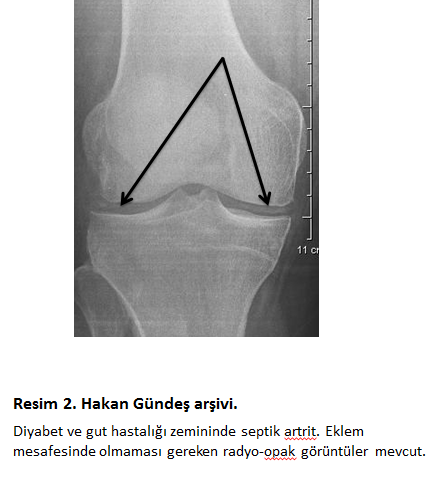

Bakteri kan dolaşımına niye karışır? Bu durum vücudumuzda her an gözlenen bir olgudur. Örneğin dişlerimizi fırçaladıktan sonra bir miktar bakteri kana karışabilir. Burada önemli olan vücudun direnç mekanizmalarıdır. Kana karışan bakteri akyuvarlar ve antikorlar tarafından bertaraf edilir. Vücudun direnç ve bağışıklık mekanizmalarının henüz tam oluşmadığı bebek ve çocuklarda bakteri bu savunma mekanizmalarından sıyrılarak ekleme ulaşabilir. Erişkinlerde ise genellikle mevcut bağışıklık sisteminin baskılanmış olması söz konusudur. Kortikosteroid tedavisi, romatoid artrit, lupus ve diyabet gibi koşullar bağışıklığın baskılanmasına yol açabilmektedir (resim 2).